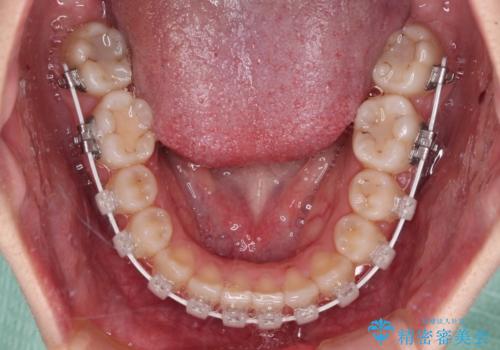

- 前歯の開咬と、上顎前歯の八重歯やデコボコを気にして来院された患者様です。

上顎歯列が狭窄していたため、急速拡大装置により上顎骨を側方に拡大し、その後ワイヤー装置にて矯正治療を行うこととしました。

上顎骨を拡大することで、八重歯やデコボコを歯列に収めることができ、下顎の歯が外に位置していた奥歯の咬み合わせも改善することができました。

スペースも短期間に獲得できるため、1年程度で治療を終えることができました。